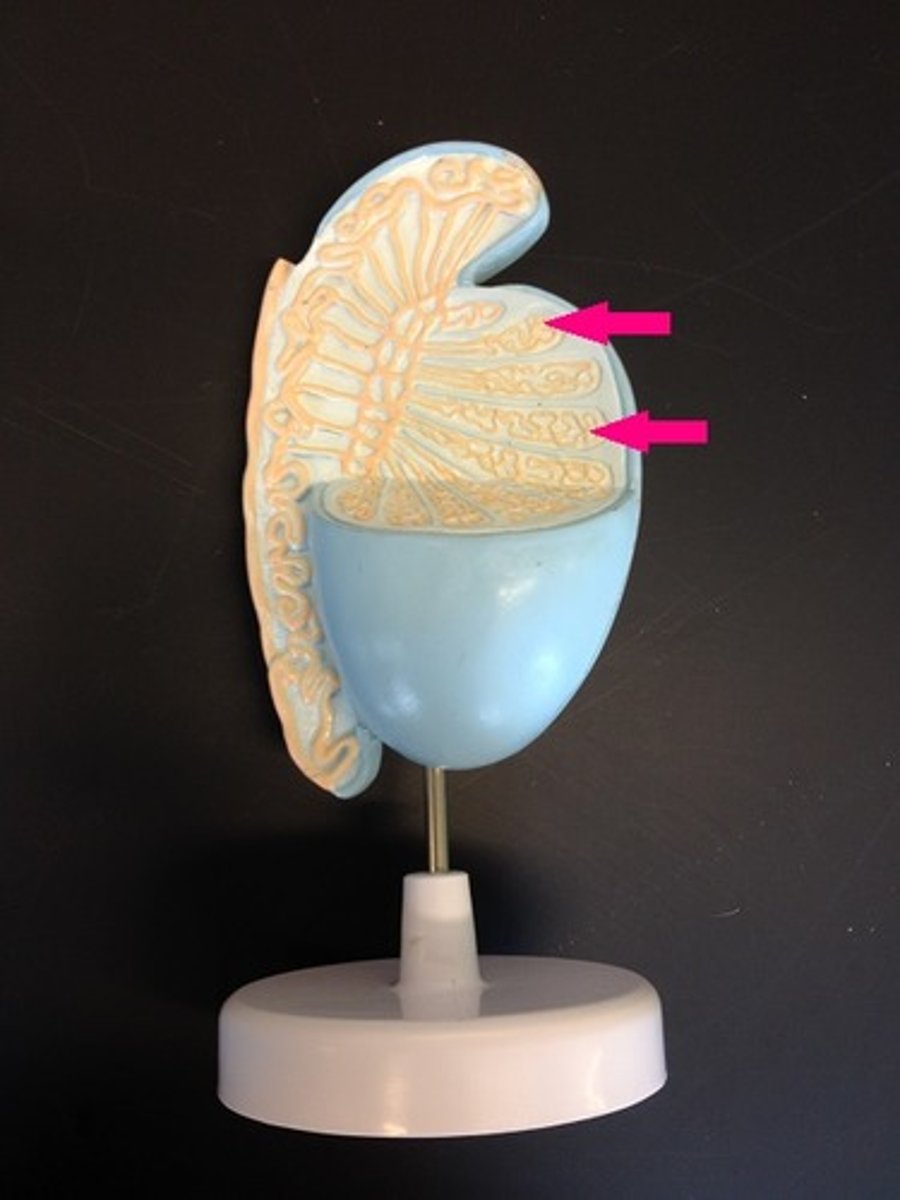

seminiferous tubules

rete testis